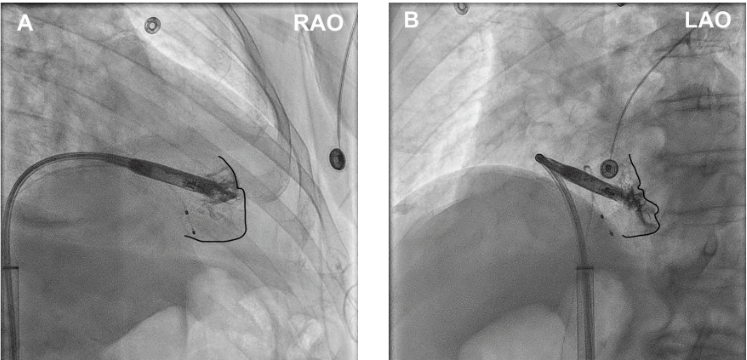

4. The importance of right anterior oblique (RAO) view. While the LAO view will define septal positioning, the RAO view will help identify TV clearance and help define “RAO space”14 with contrast injection to avoid the anterior RV recess and prevent cardiac perforation. Also, as described by Li et al,15 contrast injection in the RAO view will help define basal, mid, and apical positioning by subdividing the RV into 9 zones to avoid apical placement and optimize implant in a mid-septal position correlating with zone 2 of the ventriculogram (Figure 4). In our practice, we use an RAO 30 view to obtain these results.

Li et al. Right Ventriculography Improves the Accuracy of Leadless Pacemaker Implantation in Right Ventricular Mid-septum. Reproduced with permission under CC BY 4.0. creativecommons.org/licenses/by/4.0/.15